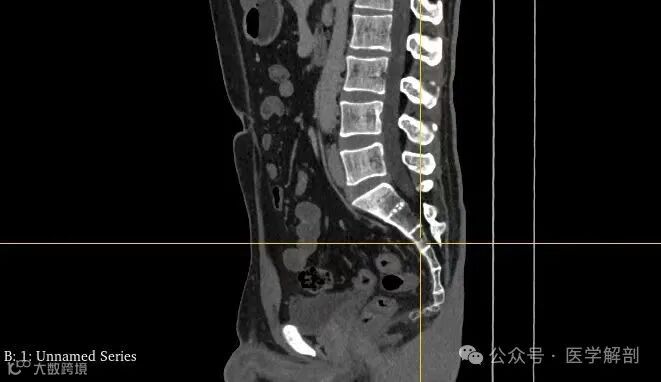

定位片

第四骶椎中部